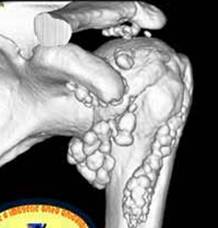

OSTEOCONDROMATOZA GLENO-HUMERALA

Ansamblul receselor articulare si spatiul bicipital sunt ocupate de osteocondroame confirmate IRM